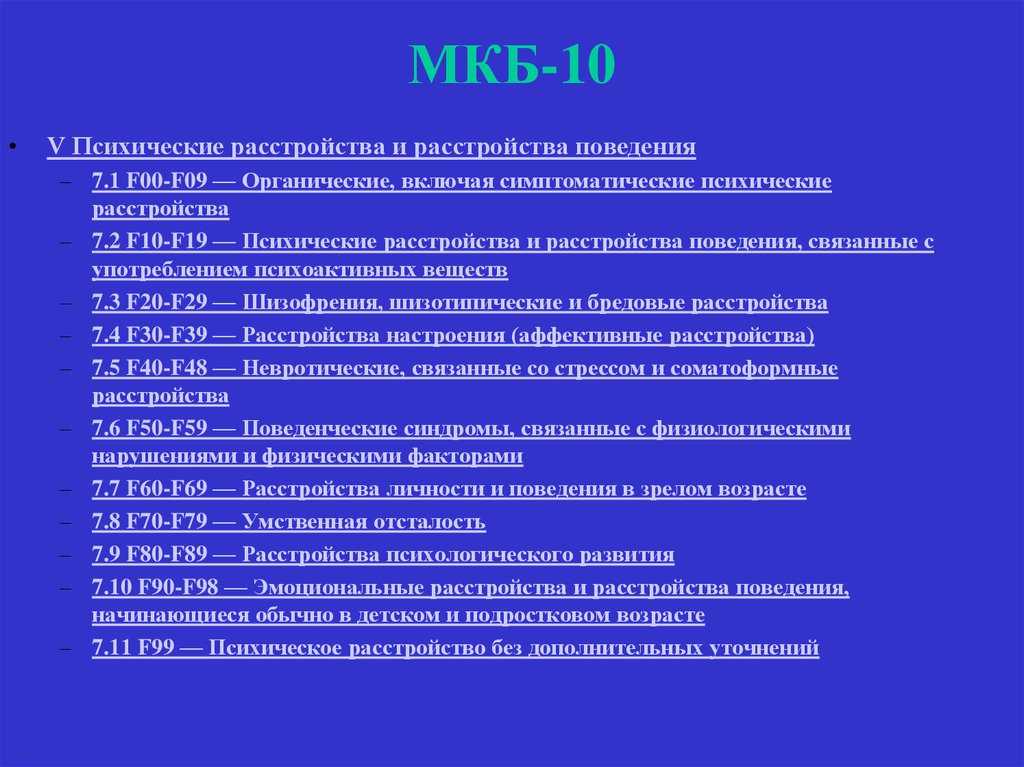

Код мкб 10 атерома головы

Код мкб 10 атерома головы 109 фото